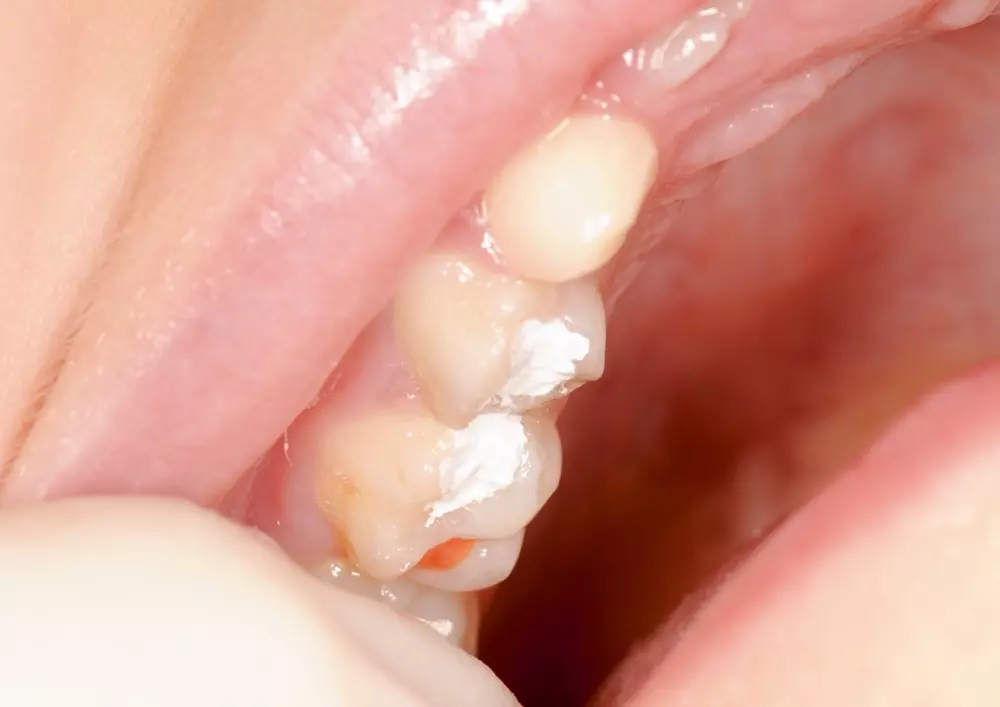

Stomatologia dziecięca. Opis przypadków leczenia

Lek. stom. Piotr Błasiński w swoim artykule opisuje przypadki leczenia pacjentów pediatrycznych. Stomatologia dziecięca, ze względu na specyfikę pacjenta, sięga po niestandardowe metody postępowania. Autor podaje algorytmy działania w sytuacjach trudnych.